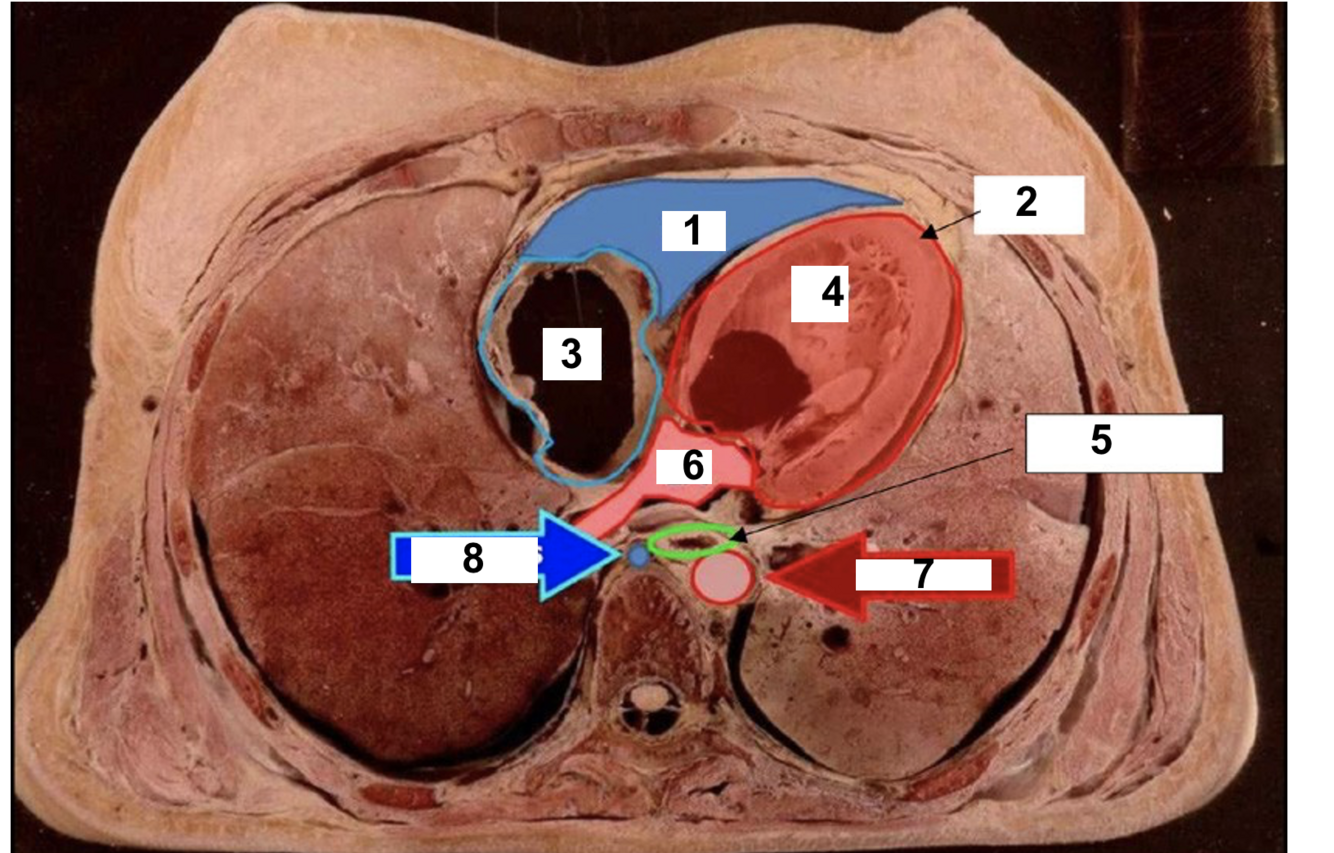

8

label

A

1. SA node

2. Inter-atrial pathways (bachmans bundle)

3. Internodal pathways

4. AV node

5. Bundle of HIS

6. RIGHT bundle branch

7. LEFT bundle branch

8. Purkinje fibres